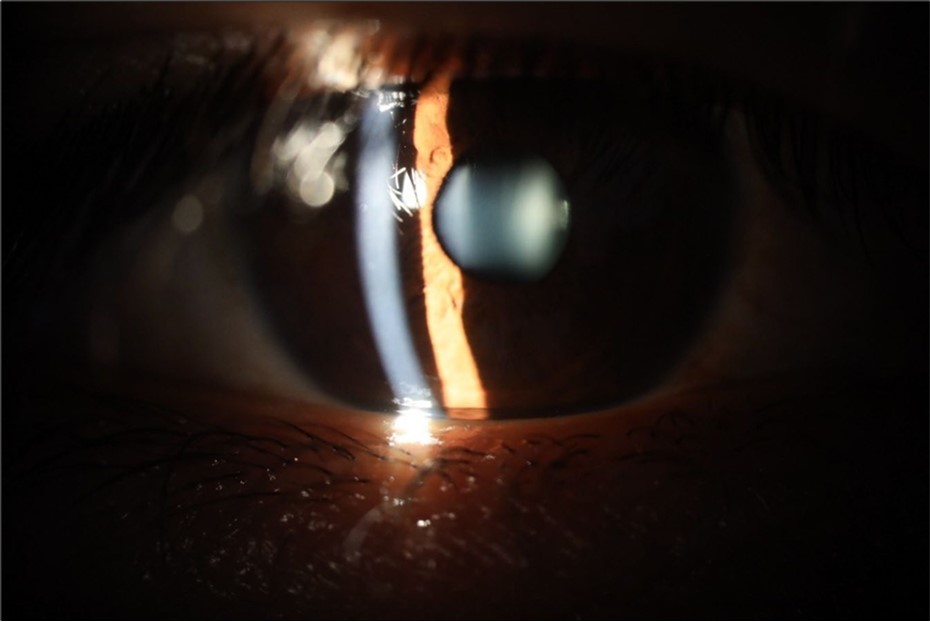

Figure 5.The slit-lamp photograph shows the anterior segment, relatively unscathed, in terms of transparent media (Cornea, crystalline and vitreous).

Figure 6.Slit-lamp examination showed a solution of continuity in the left temporal region, which fortunately only affected the conjunctiva and Tenon's capsule, while the sclera was unscathed.